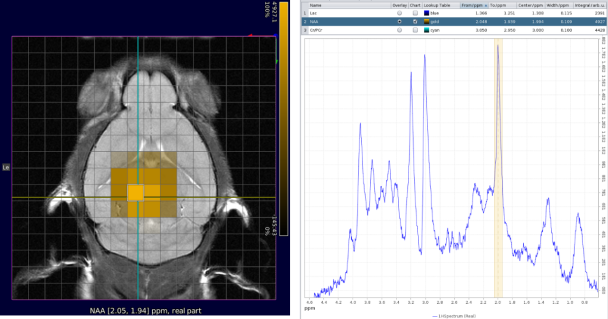

Extended spectroscopy capabilites

- AI-based baseline and phase correction

- Efficient visualization and processing of single-voxel spectroscopy and chemical shift imaging spectroscopic data (e.g., CSI) with Spectroscopy Card

- Metabolic map creation and anatomical reference image overlaying

- Spectral editing of J-coupled resonances such as lactate, γ-aminobutyric acid (GABA), glutamate, and glx (glutamate/glutamine) with MEGA-PRESS

CSI with NAA frequency mapped. Image Credit: Bruker BioSpin Group